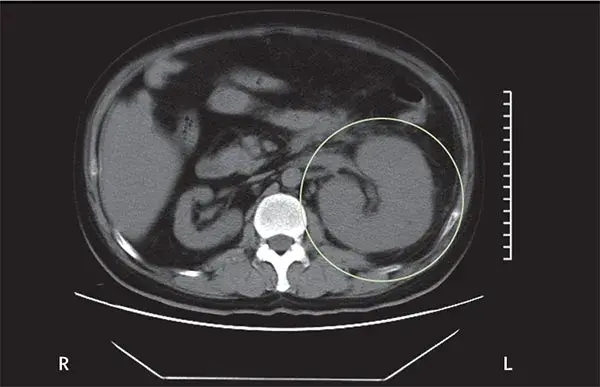

Uma causa incomum de hematúria glomerular intermitente!

Hematúria pós infecção, caso clínicos para auxiliar no entendimento de causas glomerulares comuns e raras...